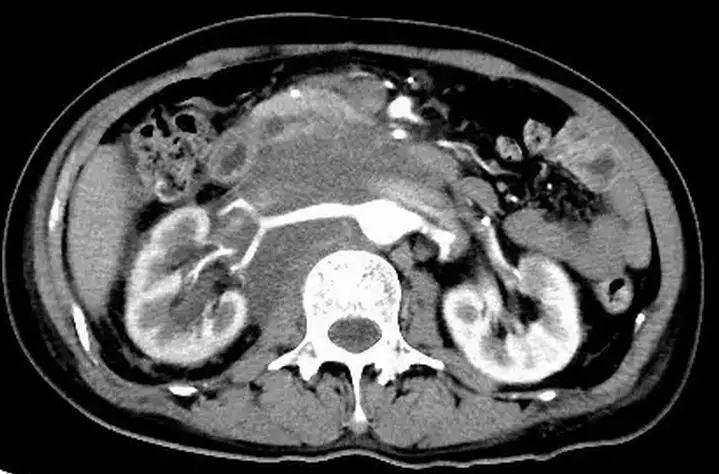

腹膜后平滑肌肉瘤常与主动脉及下腔静脉分界不清,容易侵犯腹膜后大血管,此征像较有特征。肿瘤单发多见,多发少见,体积一般较大,有包膜,形态一般呈椭圆形或分叶状,密度不均匀,肿瘤内坏死常见,出血及钙化少见,增强扫描一般呈轻度渐进性强化。肿块常与下腔静脉或其它大静脉分界不清。一般没有淋巴结转移。

增强扫描动脉期与增强扫描静脉期

从上面图像中可以看到腹膜后单发肿瘤,体积较大,边缘规则的软组织肿块,有包膜,内密度不均匀,多发低密度灶;增强扫描,不均匀轻中度强化,内有不强化中心坏死灶与囊变区,门脉期较动脉期强化明显。增强扫描呈轻度渐进性强化,没有明显钙化灶,周围无明显肿大淋巴结。病理证实为平滑肌肉瘤。